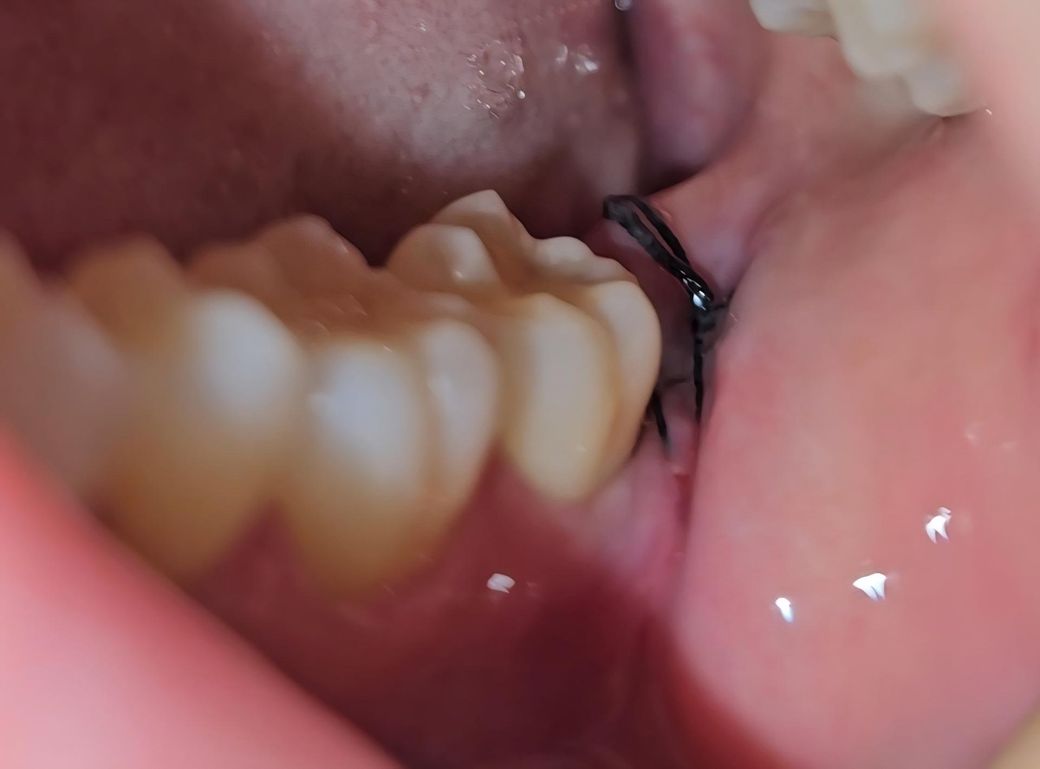

사랑니 발치 6일차인데 잘 아물고 있는 건가요?

6일차인데 아직도 입을 벌리면 불편감이 있고

발치한 부분에 칫솔이 닿으면 아픕니다ㅜ

실밥쪽에 흰색이 보이는데 저건 뭔가요?

실밥 꼬매놓은 쪽 옆(앞)에 또다른 실이 보이는데 저건 뭘까요ㅜㅜ 실밥이 2개일수도 있나요? 치아는 오른쪽 아래 사랑니 하나만 발치했습니다!

• 2번 째 사진

사진상으로 보면 발치한곳이 잘 아물고 잇는거 같습니다. 붓기가 빠지면서 실밥이 약간 느슨해 진거 같습니다.

1. 흰색물질은 치유과정에서 생기는 부산물입니다

2. 잘 아물고 있습니다

3. 봉합실 2개로 보입니다